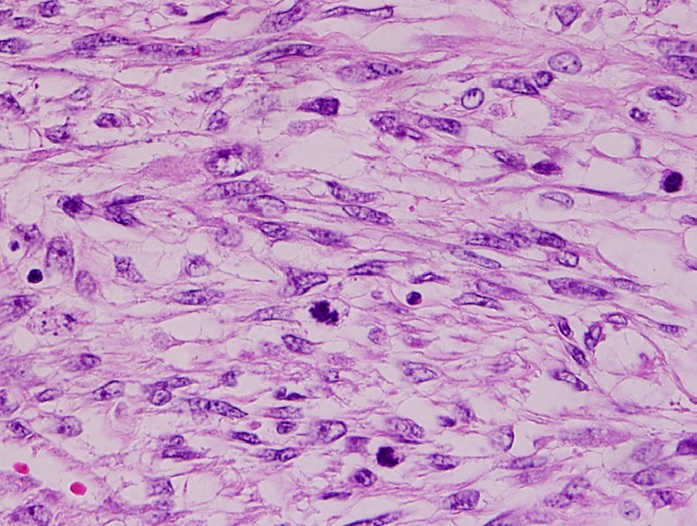

(2) 평활근육종 (Leiomyosarcoma)

Myometrium이나 endometrial stroma의 precursor cell에서 기원하는 악성 종양

• 자궁벽을 침범하거나 자궁 내강으로 돌출

High-grade atypia, high mitotic index, 그리고 종양 괴사 및 출혈이 관찰됨

• 재발률 및 전이율 높음

Histopathology of leiomyosarcoma, Wikipedia Commons